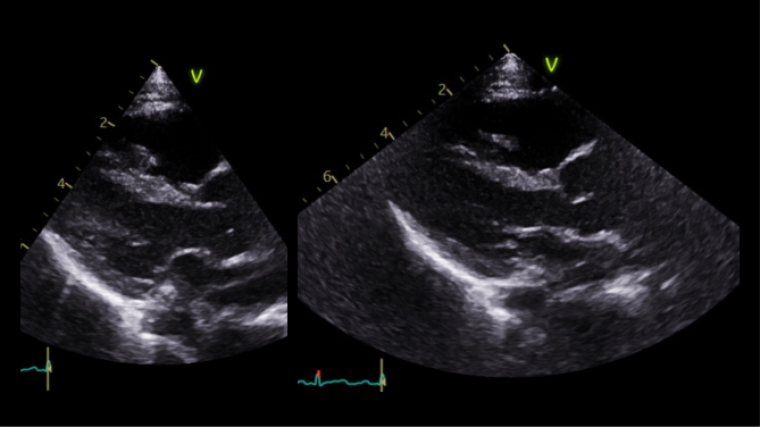

The first echocardiogram was performed when she was 8-month-old showing normal intracardiac anatomy and dimension, mild central aortic regurgitation and a moderate dilatation of the aorta with aortic annulus 13 mm (Z score +0.30), sinus of Valsalva 23.3 mm (Z score +3.71), ST junction 19.2 mm (Z score +3.48) and ascending aorta 19.1 mm (Z score +2.41), Lopez dataset.

Vol 11 Figure 3. PLAX showing dilation_Cardiovascular involvement.png